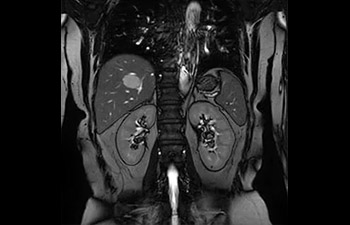

• Es una innovadora técnica de aceleración que no solo permite agilizar las secuencias, sino todo el estudio. • Implementación especial con la que las exploraciones en 2D y 3D pueden llegar a ser hasta un 50% más rápidas con una calidad de imagen prácticamente equivalente.1

• Se puede usar con todos los contrastes y con todas las regiones anatomías.